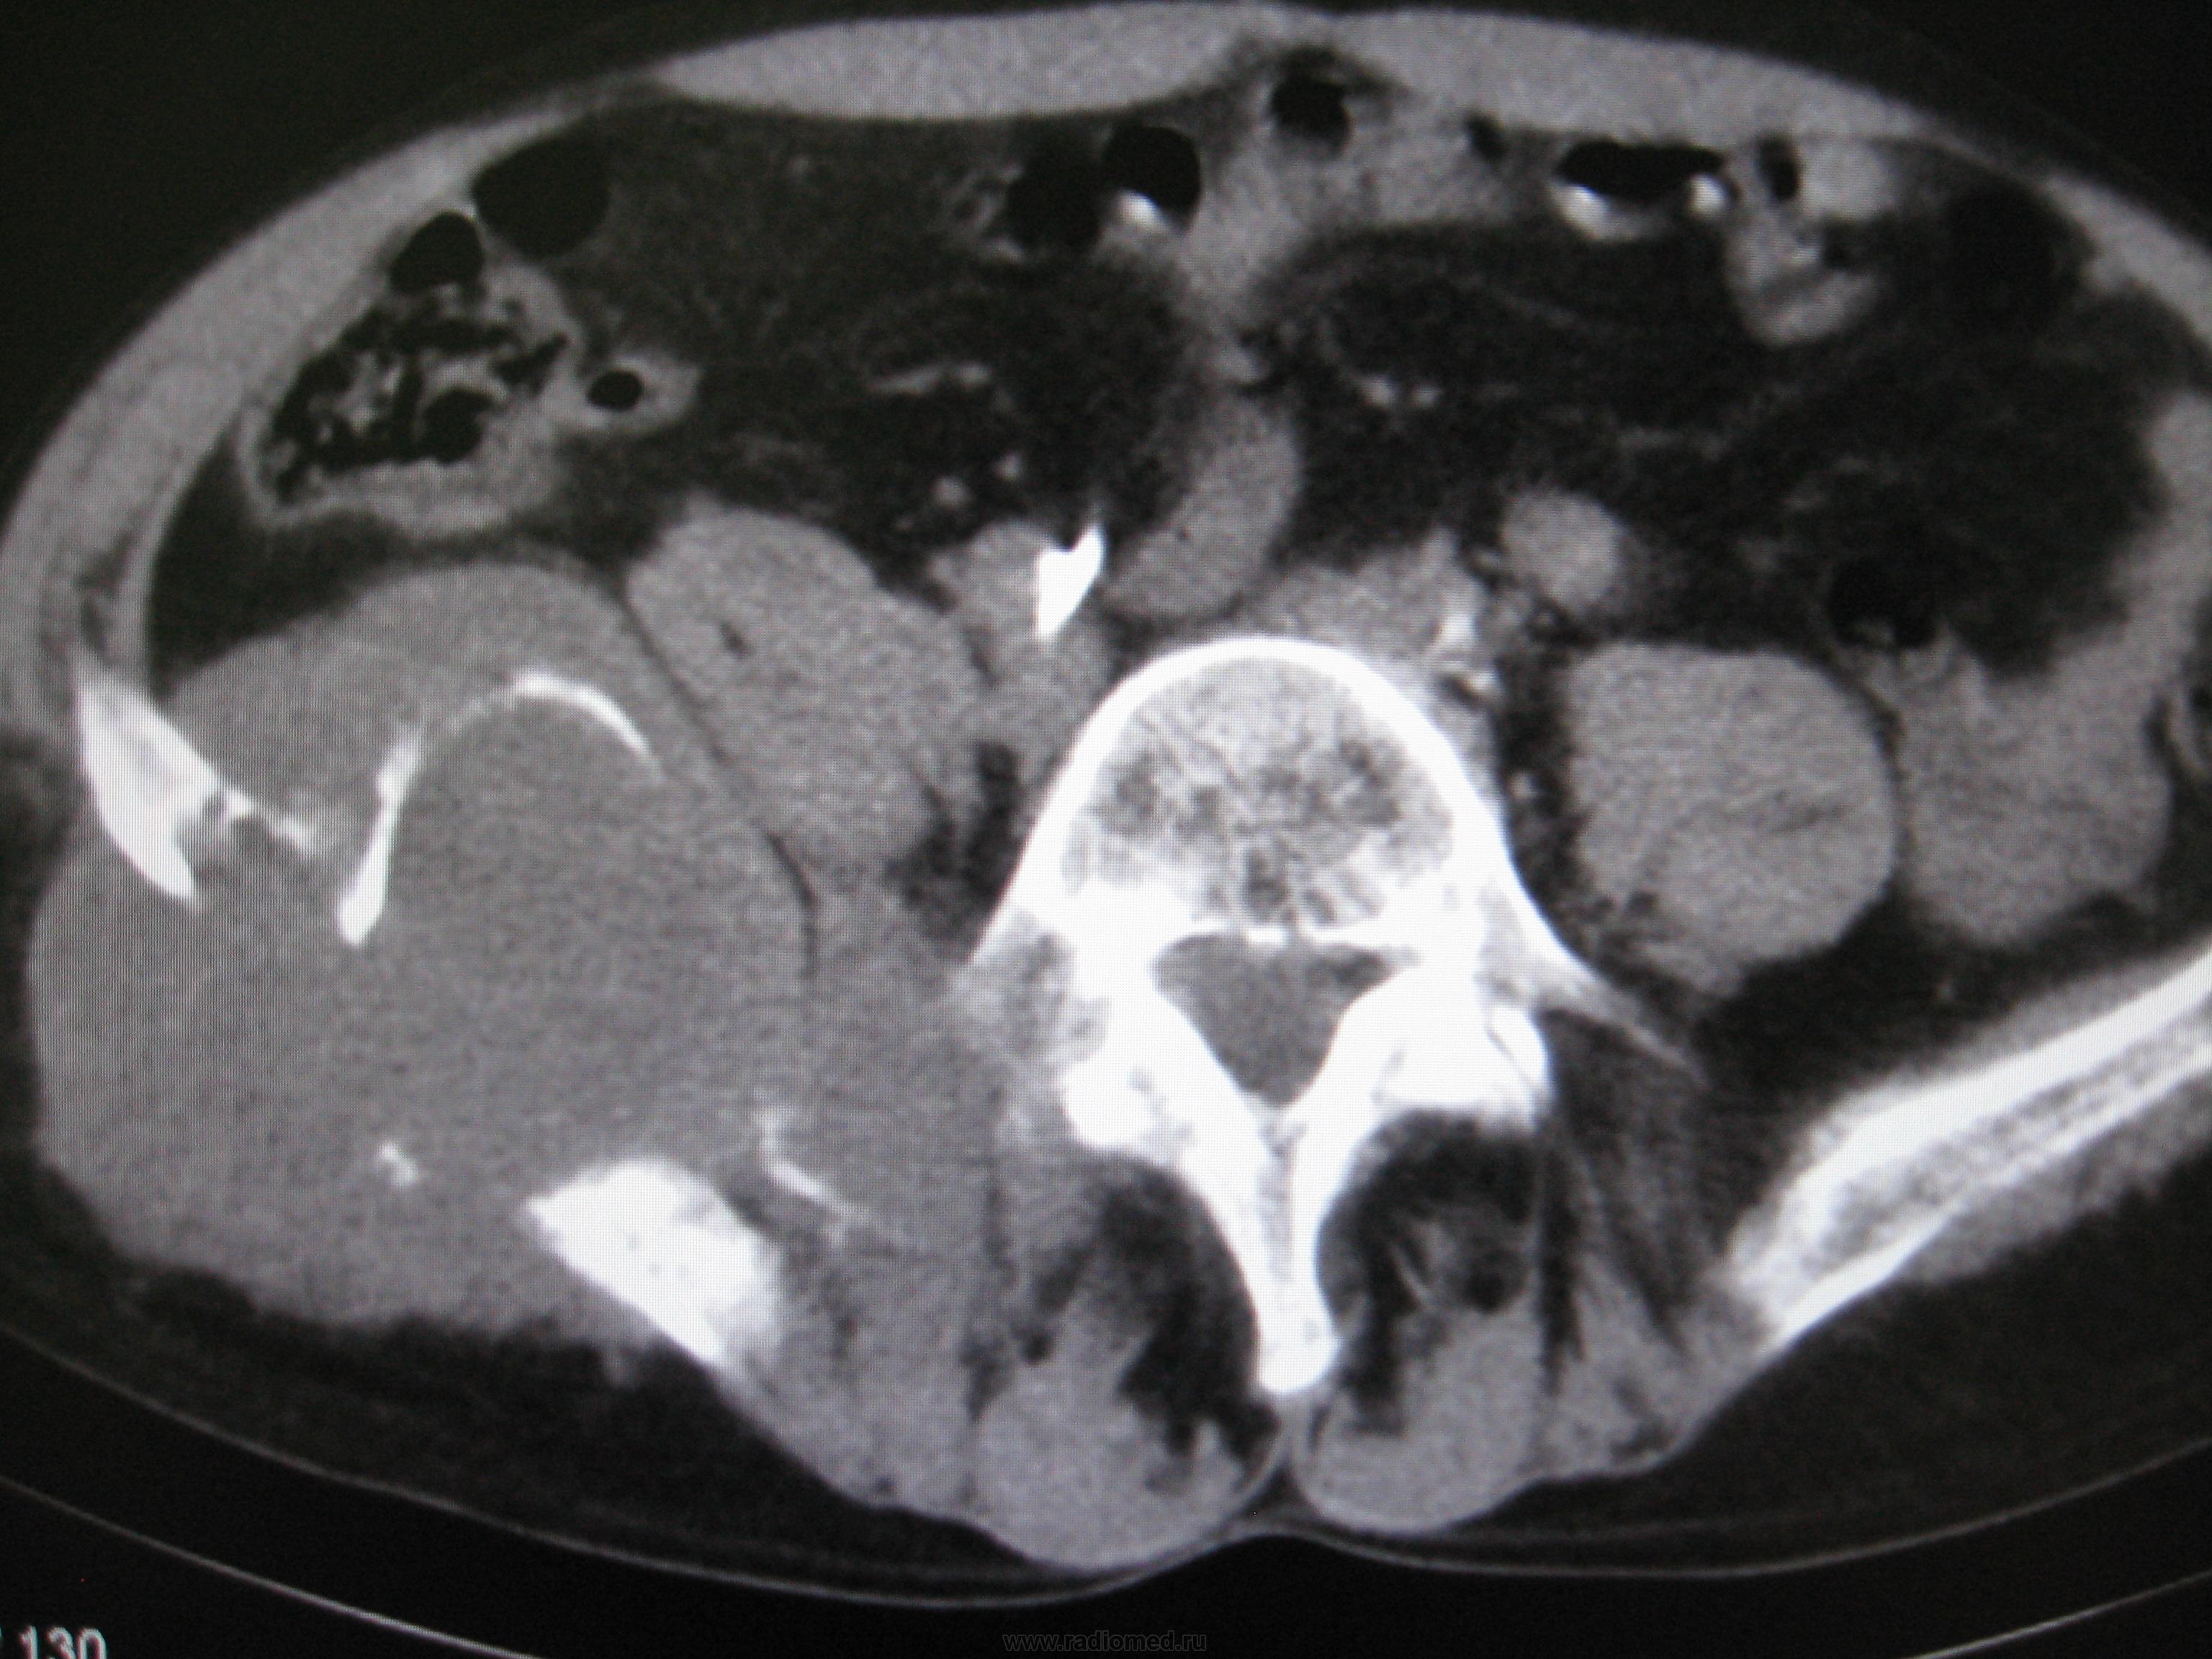

Всем доброго времени суток. Недавно занялся КТ. Вот интересное  наблюдение. Мужчина 40 лет,более полугода боли в тазу, усилились с апреля месяца. Интересно узнать ваши мнения

На мой взгляд, врача, не занимающегося КТ, имеет место злокачественное новообразование с разрушением тазовой кости и частично дуги и тела позвонка. Процесс явно "запущенный", визуализируется несколько узлов. значительных размеров "мягкотканный компонент".

Вот так красота... Не совсем понятен второй узел, у позвоночника справа, но основной, "поедающий" подвздошную кость!... саркомные дела, должно быть.

Предположим саркома Юинга.

При таких размерах и распространении опухоли, ИМХО роль гистологии не очень важна. А может быть позвонок разрушает узел метастатический?

верно. У пациента верифицированный и уже удалённый около года назад рак правой почки.

Гистологию не знаю. Так что 100%-но не скажу. Наиболее вероятный диагноз - мтс в кости таза первичный очаг -рак почки ( гистологию его к сожалению уже не помню). Консилиум наших рентгенологов (до КТ) ставил ОБК под вопросом, фиброзную дисплазию, мтс-маловероятны. С учётом наличия второго очага ОБК исключена ( на ренгенснимках - за поражение крестца убедительно высказаться нельзя), более вероятны мтс (особенно с учётом наличия верифицированного первичного очага -  мтс в кости таза к тому же являются характерными для рака почки)